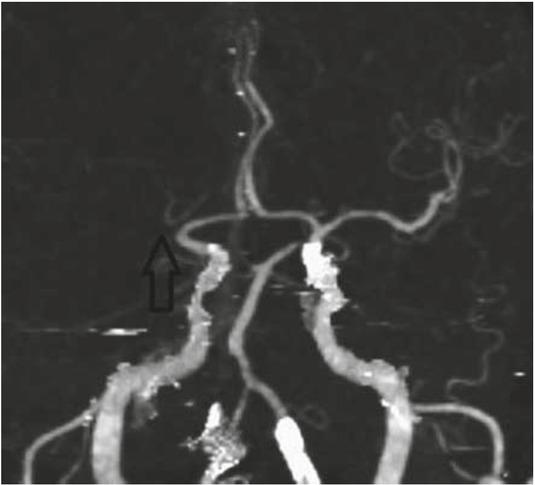

We present a case of a 77-year-old female patient with a medical history of hypertension, diabetes mellitus type 2, hyperlipidaemia and atrial fibrillation who was admitted to the general hospital with an acute onset of left-sided hemiplegia and dysarthria (National Institutes of Health Stroke Scale [NIHSS]: 4, Modified Rankin Scale [mRS]: 3). The patient was last seen without deficits 80 minutes prior to admission. The initial computed tomography (CT) scan revealed no ischaemic brain damage, and CT angiography showed right M1 MCA occlusion (Figure 1). Intravenous thrombolysis (IVT) was administered after 173 minutes and discontinued due to the sudden loss of conscience, the deviation of the head toward the left side and tonic-clonic spasms of the left extremities. The control CT scan performed under general anaesthesia showed no haemorrhagic complications. Since it was assumed that the patient had a symptomatic epileptic seizure, IVT was continued. The sedated patient was immediately transported to a tertiary institution, where a multimodal CT protocol (native CT scan, CT angiography [CTA] and CT perfusion imaging [CTP]) was performed, and the results revealed no signs of ischaemic brain damage in the symptomatic right cerebral hemisphere despite the presence of M1 occlusion and subtle (newly appeared) signs of irreversible brain damage in the contralateral MCA territory due to left ICA (“T”) occlusion. It was obvious that an additional embolic occlusion occurred during the IVT treatment. Although the time of occlusion was long, the CTP imaging results showed a penumbra in the right MCA territory and not in the contralateral left MCA territory, where irreversible brain damage occurred within 3 hours (Figure 2).

Initial imaging workup upon arrival at the general hospital. CT angiography (CTA) shows right M1 occlusion (arrow).